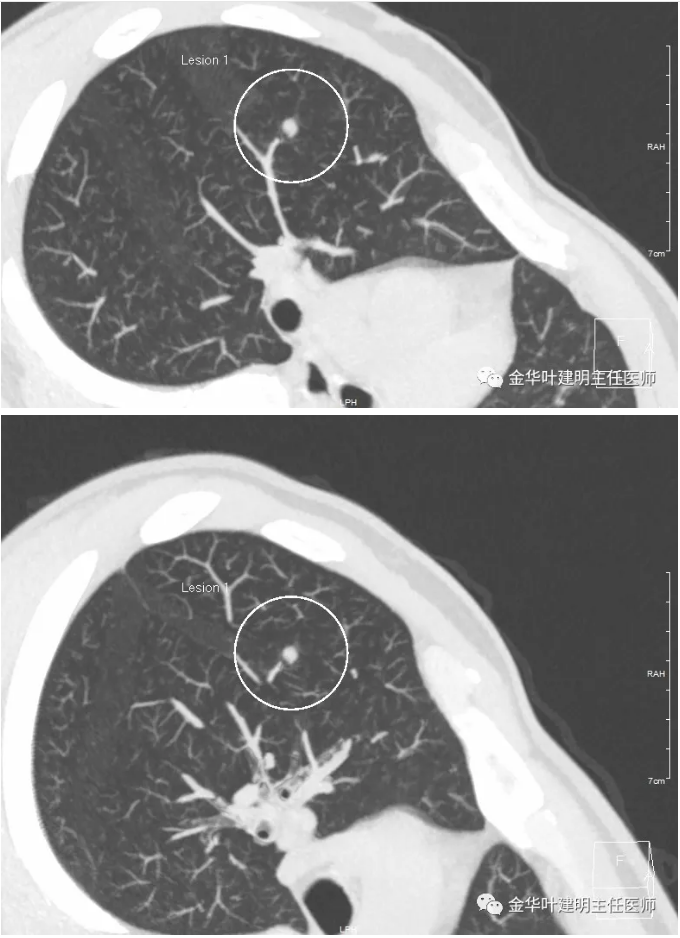

金华的某A,检查发现肺结节,年龄才30出头,没有任何症状。我们先来看他的平扫图像:

可见右肺实性结节,边缘稍不清,因整体尚小,影像特征并不好判断,那么看看薄层的靶扫描: